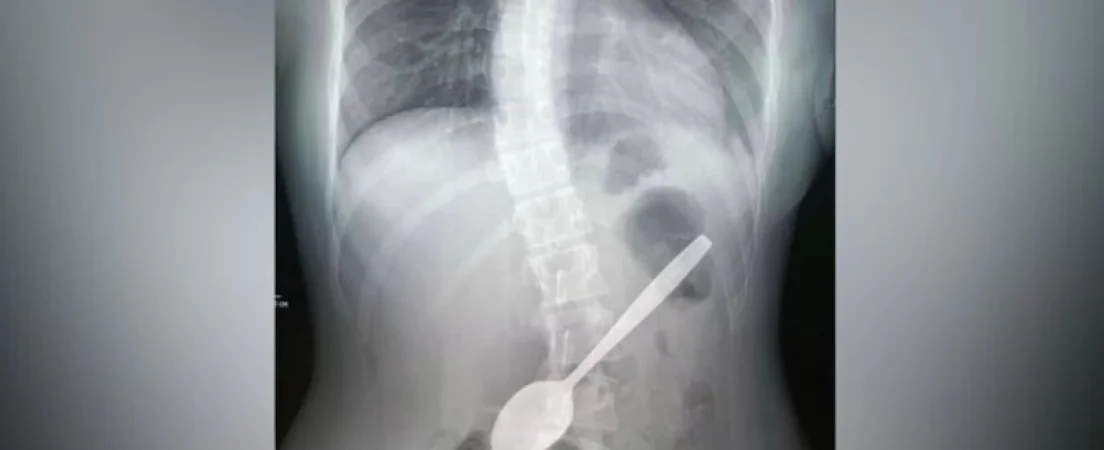

Որովայնի ռենտգեն հետազոտությամբ հաստատվել է ստամոքսում օտար մարմնի առկայությունը։ Վիրահատությունն անցկացվել է էնդոսկոպիկ եղանակով և ավարտվել է հաջողությամբ։